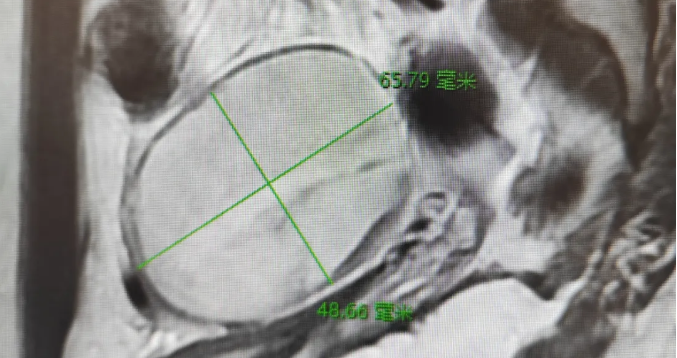

治疗过程:患者因下腹剧痛就医,经医师诊断及各项检查,影像磁共振检查显示盆腔占位,确诊为卵巢囊肿蒂扭转。妇科陈建国主任综合考虑患儿各方面因素后,与家属充分沟通,决定实施 “单孔腹腔镜卵巢囊肿剔除术”。手术顺利完成,术后蓉蓉恢复良好。单孔腹腔镜手术仅在肚脐部留下不到 2 厘米的小伤口,隐蔽不易察觉。术后 3 天,蓉蓉达到出院标准,顺利出院。